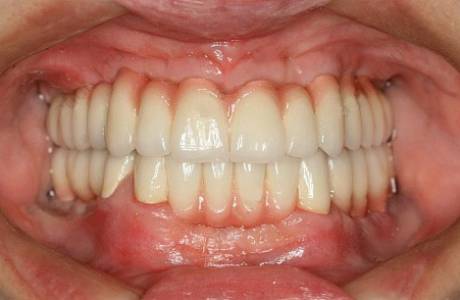

После лечения

На нижней челюсти установлены имланты. За время их приживления фронтальные зубы перелечены, восстановлены вкладками, на временных коронках зафиксирована нужная высота.

На все зубы были установлены коронки на основе диоксида циркония